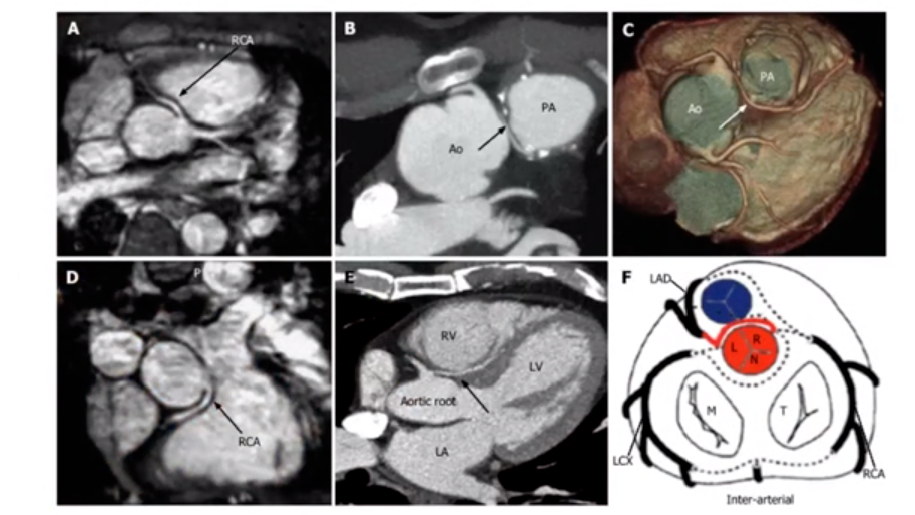

局部解剖:

图3